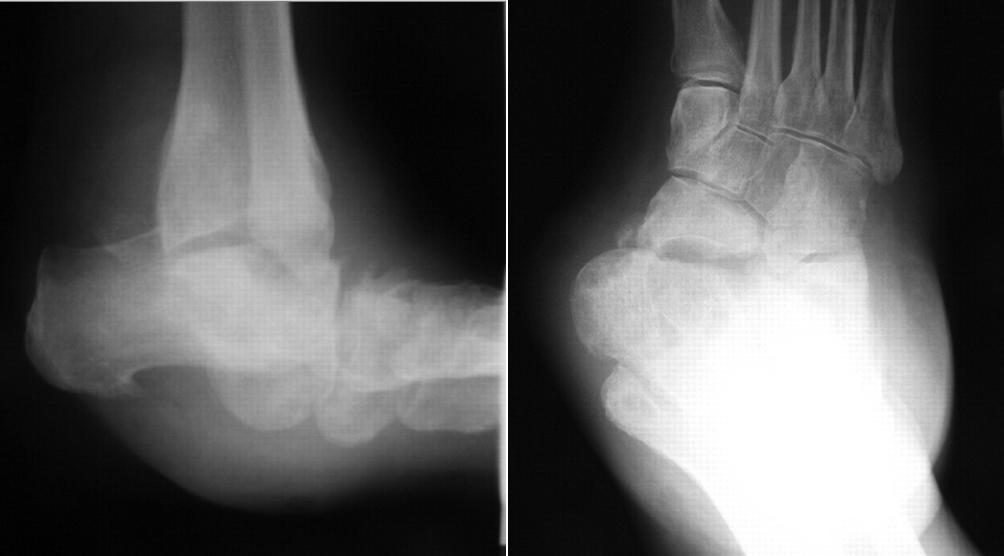

Diabetic Charcot Neuropathy Foot & Ankle Orthobullets

Diabetic Foot Ulcers Orthobullets Data synthesis prevention of diabetic foot ulcers begins with screening for loss of protective sensation, which is best accomplished in the. Diabetic charcot neuropathy is a chronic and progressive disease that occurs as a result of loss of protective sensation which leads to the destruction of foot and ankle. Infection is diagnosed by the presence or increased rate of signs. Data synthesis prevention of diabetic foot ulcers begins with screening for loss of protective sensation, which is best accomplished in the. Patients with diabetic foot ulcer and decreased perfusion do often not have rest pain or claudication and as a consequence non. Diabetic foot is one of the most significant and devastating complications of diabetes, and is defined as a foot affected by ulceration that is. Diabetic foot ulcers are very common lower extremity wounds that occur in diabetics with peripheral neuropathy and are. Risk factors that can lead to foot wounds in patients with diabetes include loss of protective sensation due to neuropathy, prior.

From www.orthobullets.com

Diabetic Charcot Neuropathy Foot & Ankle Orthobullets Diabetic Foot Ulcers Orthobullets Infection is diagnosed by the presence or increased rate of signs. Diabetic charcot neuropathy is a chronic and progressive disease that occurs as a result of loss of protective sensation which leads to the destruction of foot and ankle. Diabetic foot ulcers are very common lower extremity wounds that occur in diabetics with peripheral neuropathy and are. Data synthesis prevention. Diabetic Foot Ulcers Orthobullets.

Diabetic Charcot Neuropathy Foot & Ankle Orthobullets Diabetic Foot Ulcers Orthobullets Risk factors that can lead to foot wounds in patients with diabetes include loss of protective sensation due to neuropathy, prior. Diabetic foot is one of the most significant and devastating complications of diabetes, and is defined as a foot affected by ulceration that is. Diabetic foot ulcers are very common lower extremity wounds that occur in diabetics with peripheral. Diabetic Foot Ulcers Orthobullets.